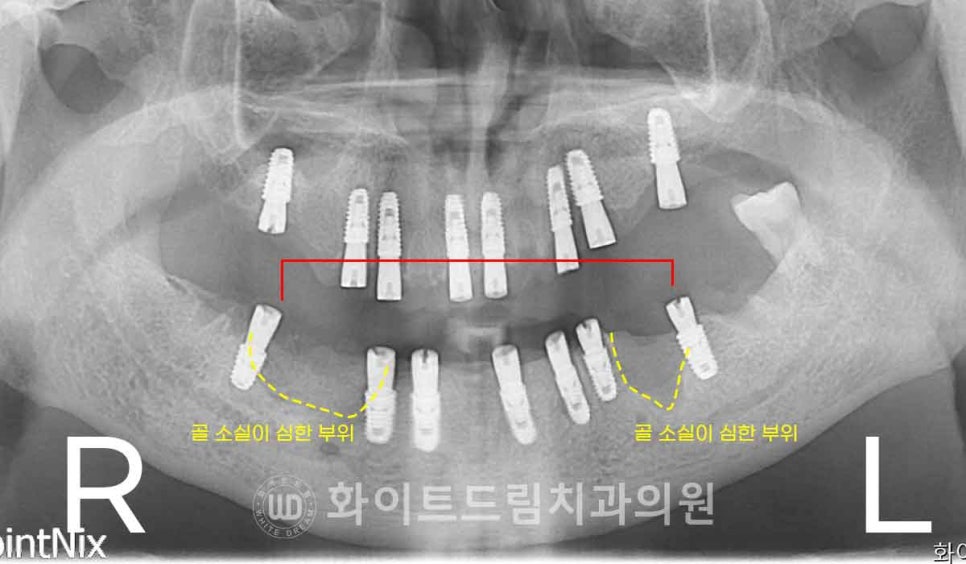

▲ 환자분의 치료 전 X-RAY 사진입니다.

상/하악 치아들이 더 이상 사용이 불가능할 정도로 심한 치아 마모와 손상을

입은 상태이고 하악 롱브릿지로 연결되어 있는 지대치는

심한 치주염으로 광범위한 뼈 흡수가 진행된 것이 확인됩니다.

염증으로 인해 골 소실이 심했던 부위는 피하고,

상대적으로 잇몸뼈가 남아 있는 부위로 임플란트를 식립하였습니다.

이렇게 하면 임플란트의 초기 고정력을 안정적으로 확보할 수 있을 뿐만 아니라,

불필요한 뼈이식을 줄여 환자분의 부담을 덜 수 있는 장점도 있습니다.